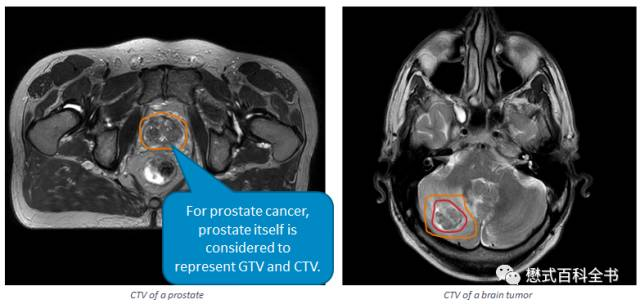

GTV(Gross Tumor Volume), 肿瘤靶区:指的是我们影像图片中所能够直观观察到的肿瘤的体积,包括淋巴结和侵犯到周围的组织器官。

CTV(Clinical Tumor Volume), 临床靶区:指包括前面的GTV,再加上一些亚临床病变,如水肿。CTV>GTV。